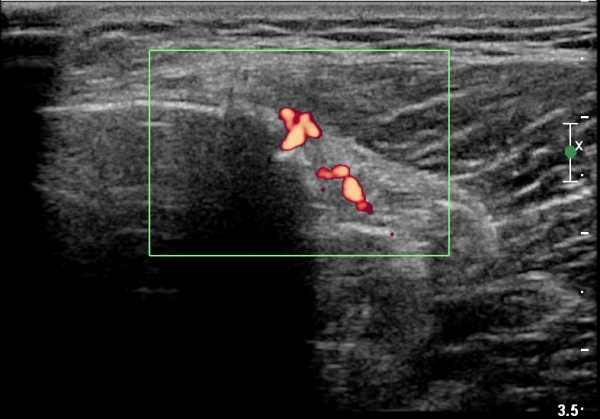

[¹«¸­] °æ°ñ ÇǷΰñÀý ÃÊÀ½ÆÄ¼Ò°ß(sonographic findings of stress fracture of tibia)

¿ìÃø ¹ß¸ñ°ú ¾Æ·§´Ù¸® ÅëÁõ(±â°£ 2ÁÖ)

±º´ë¿¡ ÀÔ´ëÇÏ¿© ÈÆ·ÃÀ» ¹ÞÀº º´·ÂÀÌ Àִ ȯÀÚ´Â ¾à 2ÁÖ ÀüºÎÅÍ ¹ß¸ñ ºÎÀ§ÀÇ ÅëÁõÀÌ ÀÖ´ø Áß

ÃÖ±Ù¿¡´Â ¹ß¸ñ À§ ¾Æ·§´Ù¸®¿¡ ÅëÁõÀÌ ¹ß»ýÇÏ°í ½ÉÇÏ°Ô °ÉÀ¸¸é ½ÉÇØÁö´Â ¾ç»óÀÓ

¾Æ·§´Ù¸® Áß°£ ºÎÀ§¿¡ °æ¹ÌÇÑ ¿¬ºÎÁ¶Á÷ ºÎÁ¾ÀÌ °üÂûµÇ°í ¾à°£ÀÇ ±¹¼ÒÀû ¾ÐÅëÀ» º¸ÀÓ.

ÃÊÀ½ÆÄ °Ë»ç